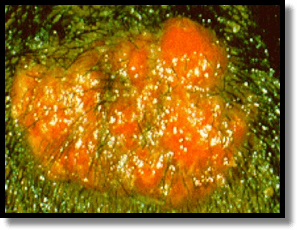

The Kerion is not likely superinfected!

- They may look disgusting and have purulent drainage, but they are not commonly superinfected. Antibiotics are usually not necessary… and should not be administered in lieu of systemic antifungals.